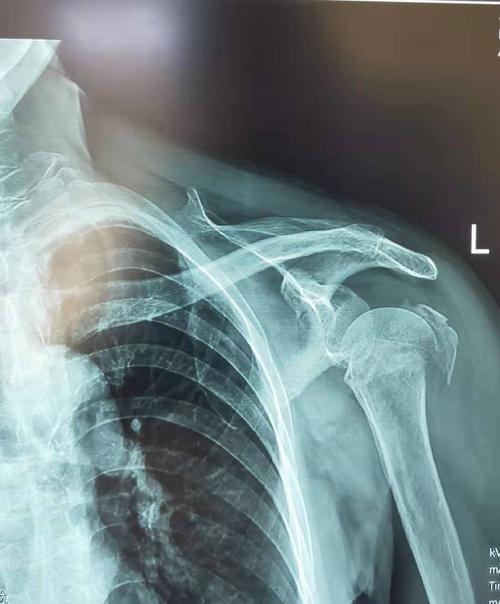

左肱骨近端骨折图片

左肱骨近端骨折图片,股骨近端骨折

肱骨近端骨折

左侧肱骨近端骨折

肱骨近端骨折图片

肱骨近端骨折分型

肱骨近端骨折neer分型